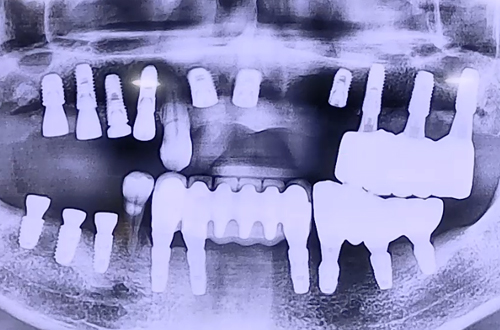

BEFORE

환자분은 이전 왼쪽에 임플란트를 진행하셨었고,

임플란트가 되지 않은 오른쪽 위아래 어금니와 위 앞니가 심하게 흔들거려서

거의 왼쪽으로만 식사를 하고 계시는 상태에서 내원해 주셨습니다.

때문에 오른쪽 위아래 어금니와 윗니 앞니를 임플란트를 통해서 단단히 하고

치아의 기능을 회복시켜드리는 방향으로 치료 계획을 세웠는데요.